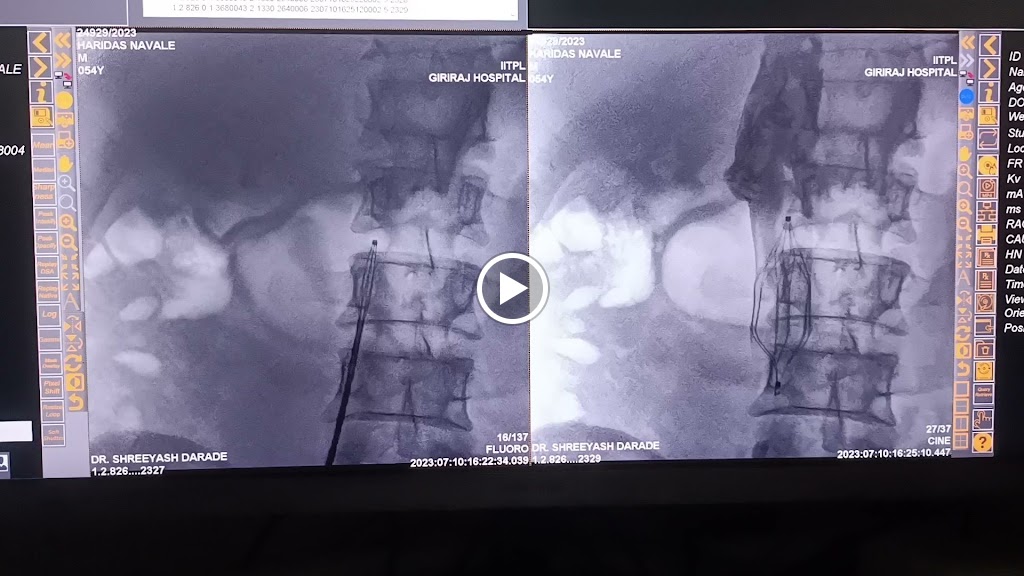

Full Time Cardiologist in Baramati. OPD and IPD Facilities. 24 hr emergency services. ECG 2D Echo Stress Test (TMT) 24 hr Ambulatory BP monitoring 24 hr Holter ECG monitoring Angiography Angioplasty, emergency Angioplasty (PAMI) Pacemaker Chest Pain Clinic Heart Failure Management Hypertension treatment Diabetes Treatment

Best heart care hospital in baramati. Dr.Darade cardiologist good diagnosis and treatment. My father had heart attack. sir did Angiography nd Angioplasty. Excellent results and facilities for heart patient. Thank you

Dr. Darade Cardiologist sir accurately diagnosed my heart attack. Sir did my emergency Angiography and Angioplasty in his camp. I'm good now. No complaints. Very fast diagnosis and treatment. Heart patient.